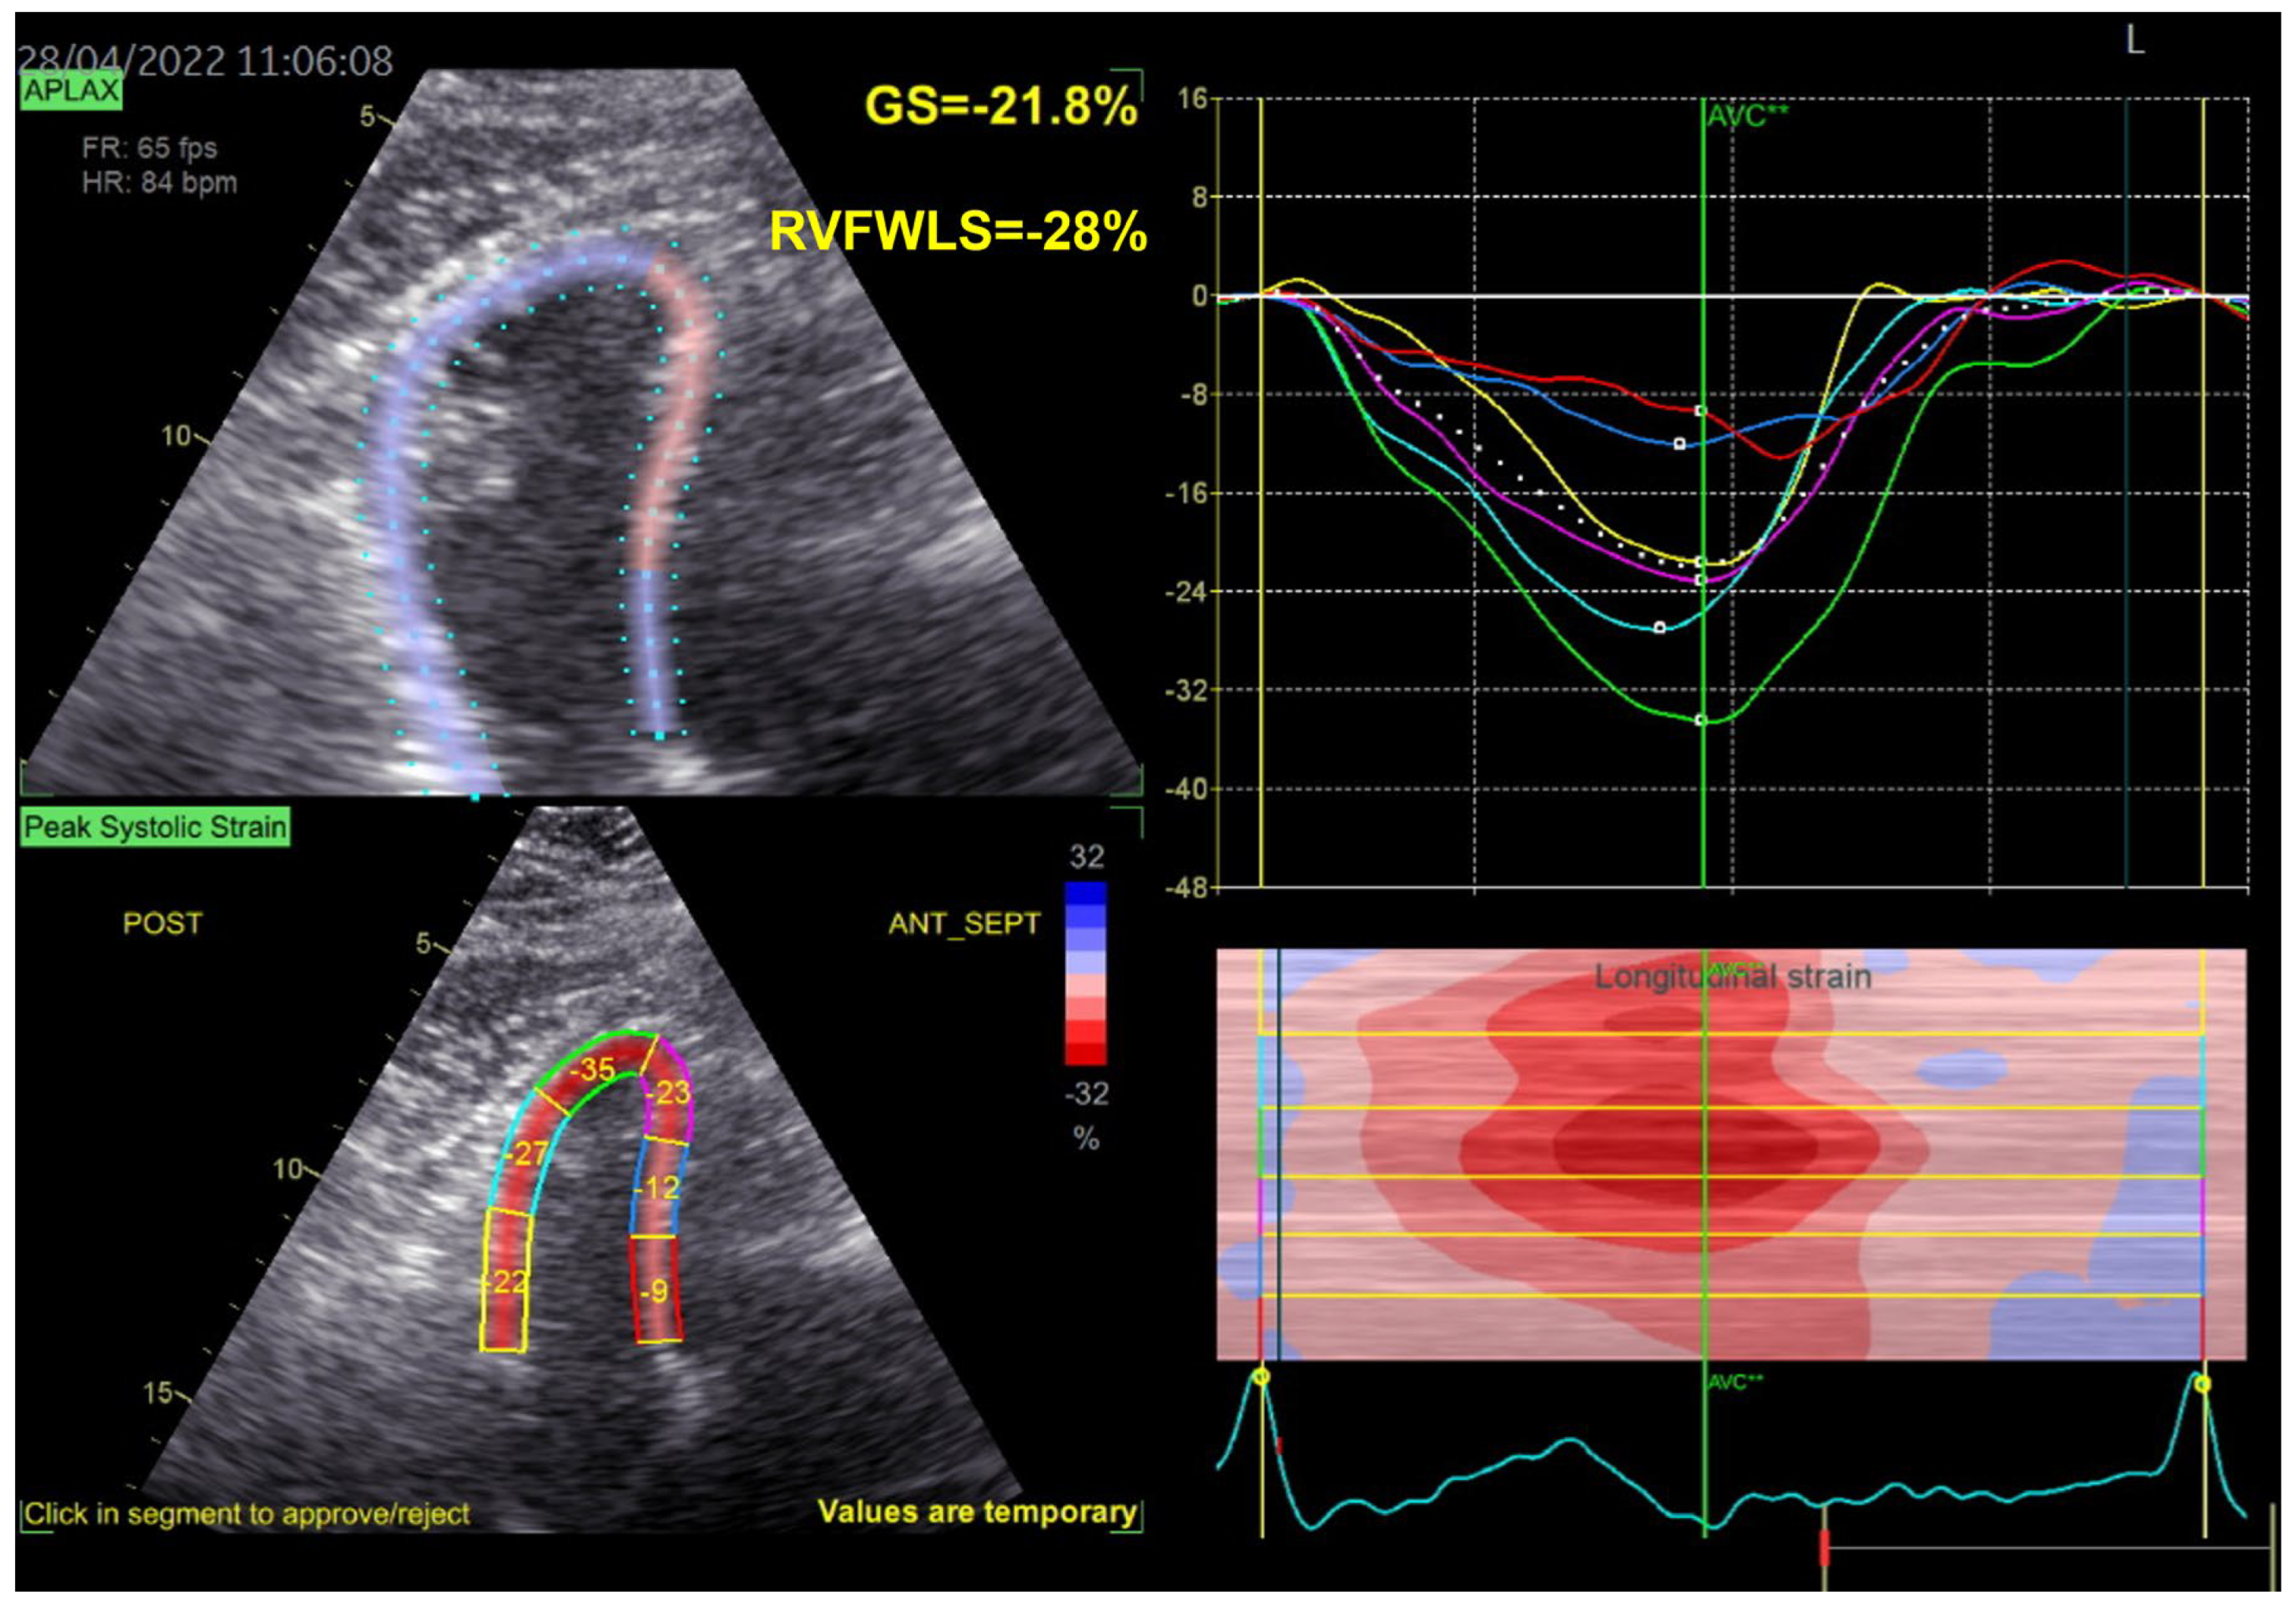

| Echocardiography | Hypokinetic non-dilated cardiomyopathy LVEF = 42% Mild mitral regurgitation IAS aneurysm | Hypokinetic non-dilated cardiomyopathy LVEF = 34% Mild mitral regurgitation IAS aneurysm | Left ventricular concentric hypertrophy LVEF = 54% |

| Cardiac magnetic resonance imaging | Hypokinetic non-dilated cardiomyopathy Left ventricular non-compaction LVEF = 50% | Hypokinetic non-dilated cardiomyopathy Regional sub-epicardial fibrosis LVEF = 41% | Not carried out |